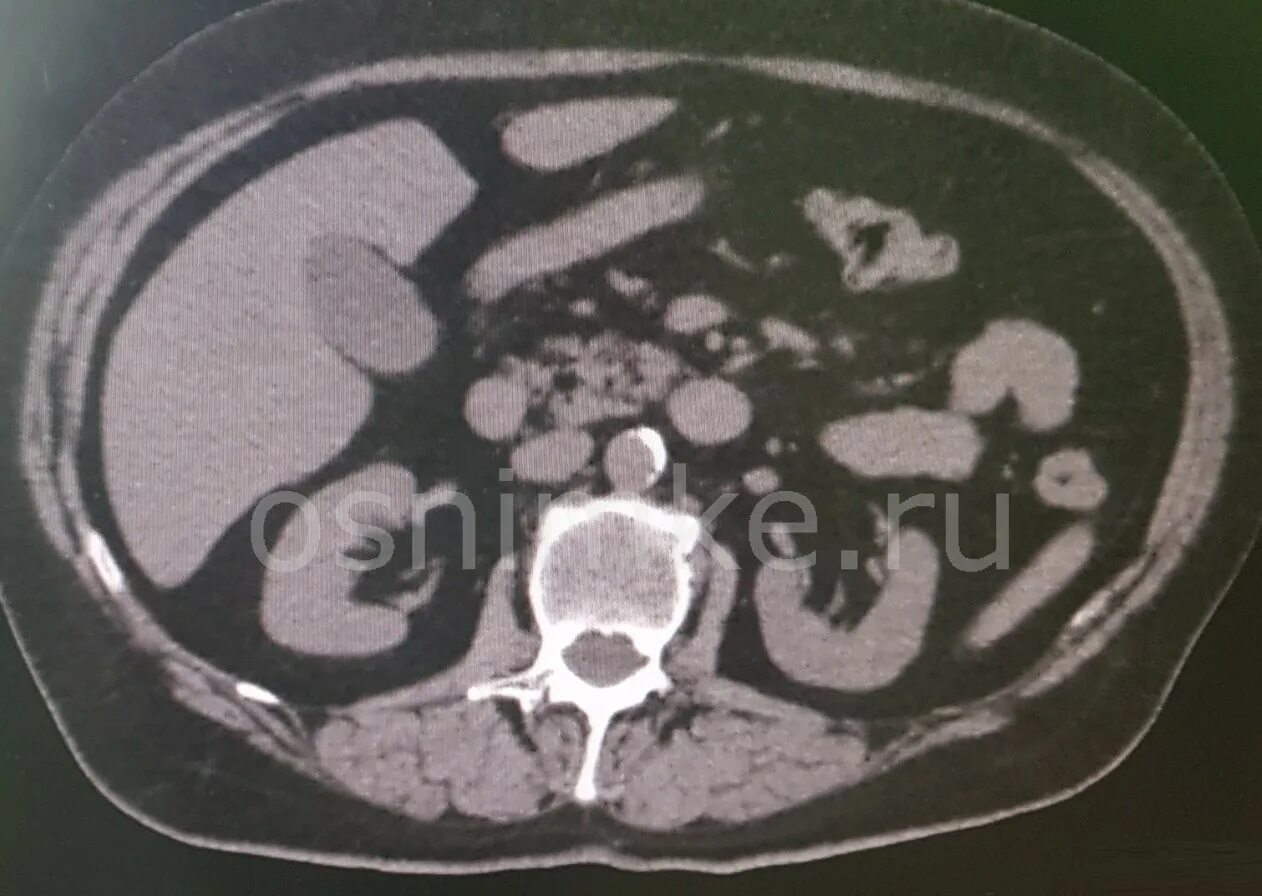

Кт почек с контрастированием как проводится